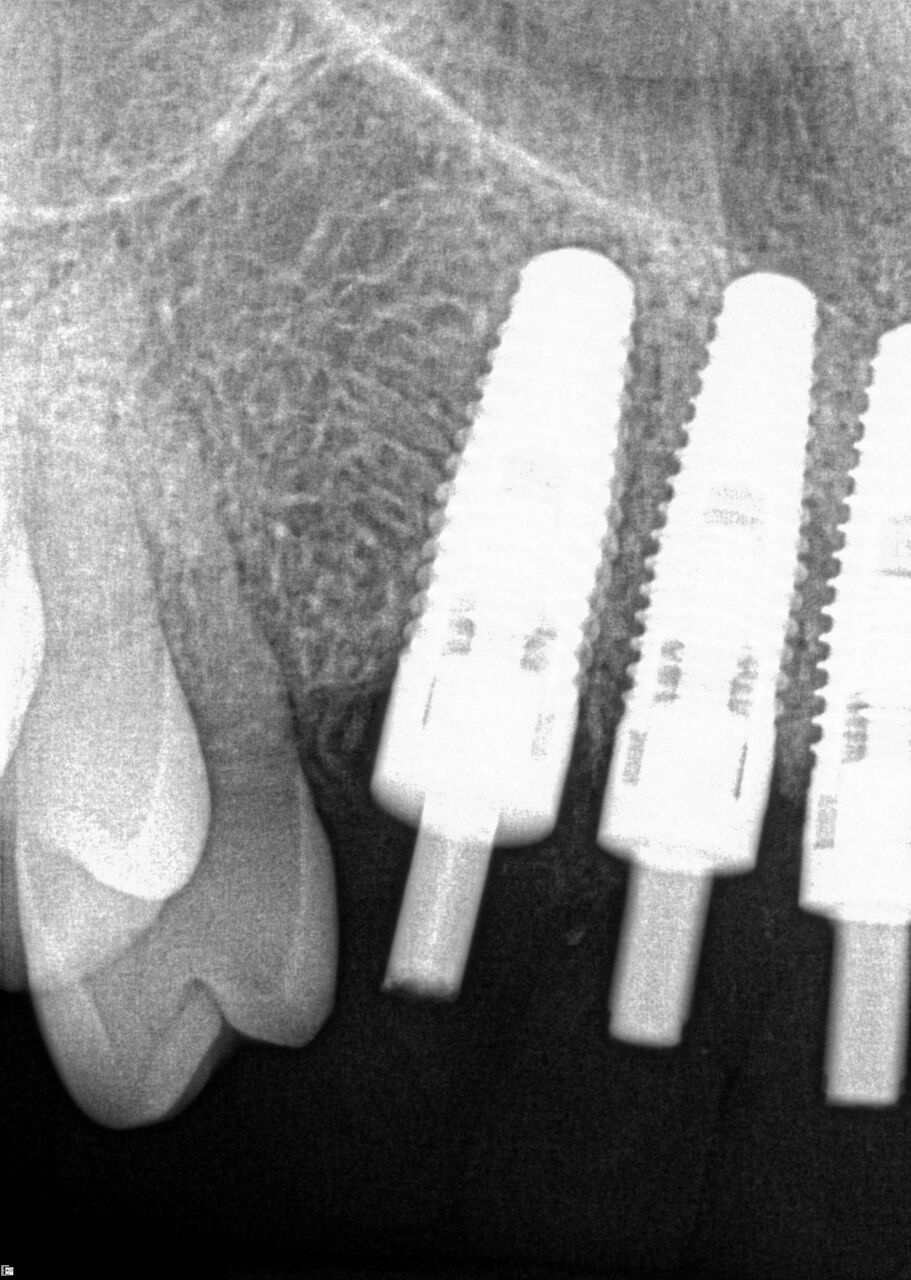

(20.) 6-month integration confirmation of Nos. 6 through 10.

Figure 20

(21.) 6-month integration confirmation of Nos. 6 through 10.

Figure 21

A 42-year-old man presented with a very loose bridge on Nos. 6 through 9 with periodontally compromised retainers on Nos. 6 and 9 (Figure 17 through Figure 19), and endodontically involved No. 10 with a calcified canal. Teeth Nos. 6, 9, and 10 were extracted, the sockets fully debrided, and pontic soft tissue on Nos. 7 and 8 sculpted to be symmetrical in soft tissue contour with the contralateral lateral incisor and central incisor locations. Implants were secured in position Nos. 6 through 10 (Figure 20) in excess of 45 Ncm, the bone was milled to provide unimpeded seating of temporary abutments, and temporary crowns were fabricated chairside and adjusted to be out of occlusion in centric relation and all excursions. The temporary crowns were cemented after extrusion of excess cement extraorally and the patient was prescribed antibiotics, analgesics, and instructed in postoperative care particular to immediately provisionally restored implants. At 6 months, integration was confirmed (Figure 20 through Figure 23) and after placement of scanning abutments, the implants and soft tissues were scanned. Final crowns were fabricated from the scanned images and were cemented after extrusion of excess cement extraorally (Figure 24 through Figure 26), and oral hygiene procedures were reviewed.